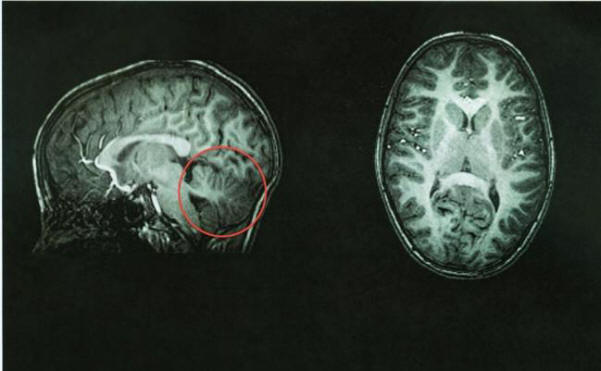

A tomográfia után az orvosok azonnal azonosították a probléma forrását – annak okait kisagy nem volt jelen. A hely, ahol üresnek kell lennie. ezt az agy területét cerebrospinális folyadékkal töltötték meg, biztosítja védelem a betegség ellen. A kisagy kb. 10% -át veszi igénybe az agy teljes térfogata, de az idegsejtek 50% -át tartalmazza.

Kínai nő agyi képalkotása kisagy nélkül